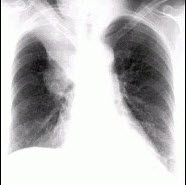

75、单项选择题

女,根据其正常骨盆影像图像,判断其最可能的年龄()

A.69岁左右

B.59岁左右

C.49岁左右

D.19岁左右

E.39岁左右